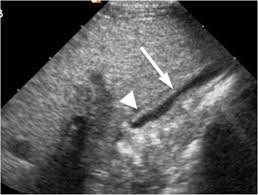

Normal Gallbladder Size on Ultrasound

Normal gallbladder volume on ultrasound indicates:

- Properly shaped

- Clear bile inside

- There are no sludge or stones

- Smooth and thin walls

- Standard size to be used for the fasting state